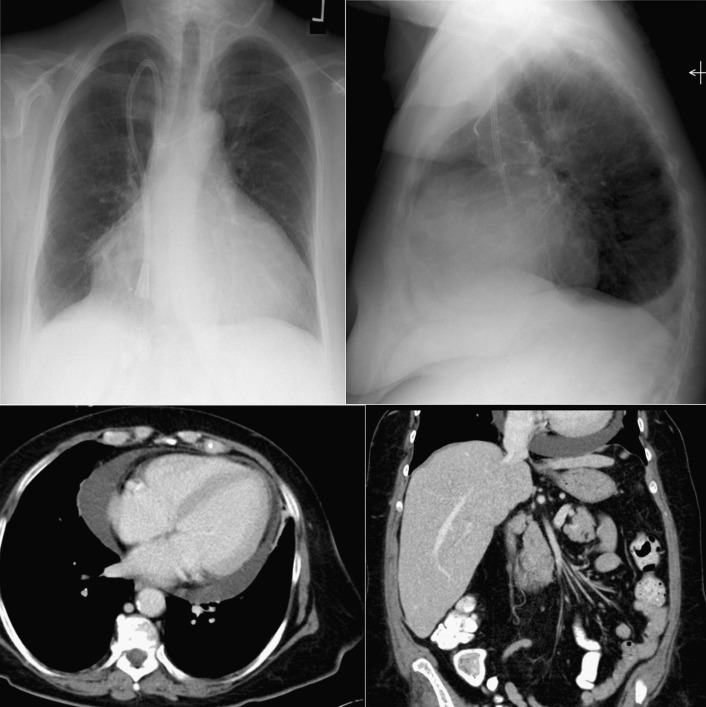

A pericardial effusion ( Figs. 16-1 to 16-15 ) is often suggested on the frontal chest radiograph by a smoothly distended, “flasklike” CPS. More than 500 mL of fluid must be present before the change in the CPS is fairly obvious. A flasklike appearance may be caused by myocardial disease as well; scrutiny of the hilar vessels may distinguish the two. In the presence of pericardial effusion, the hilar vessels are covered (the pericardium runs up onto them and obscures them). In the presence of myocardial disease, the hilar vessels are unusually prominent as they are distended under higher than usual pressure.

In a minority of patients with pericardial effusion, on the lateral radiograph, a stripe of radiolucent epicardial fat, a “fat line,” may be visible anteriorly, suggesting fluid in the pericardial space. A stripe greater than 2 mm is abnormal. This “pericardial stripe sign” is more easily seen in adults than children (more fat!).

A prominent azygous vein, superior vena cava, or inferior vena cava suggests cardiac tamponade.

Echocardiography is the diagnostic test of choice for the evaluation of pericardial effusions. Pericardial tamponade remains a clinical diagnosis, strengthened by supportive echocardiographic findings.